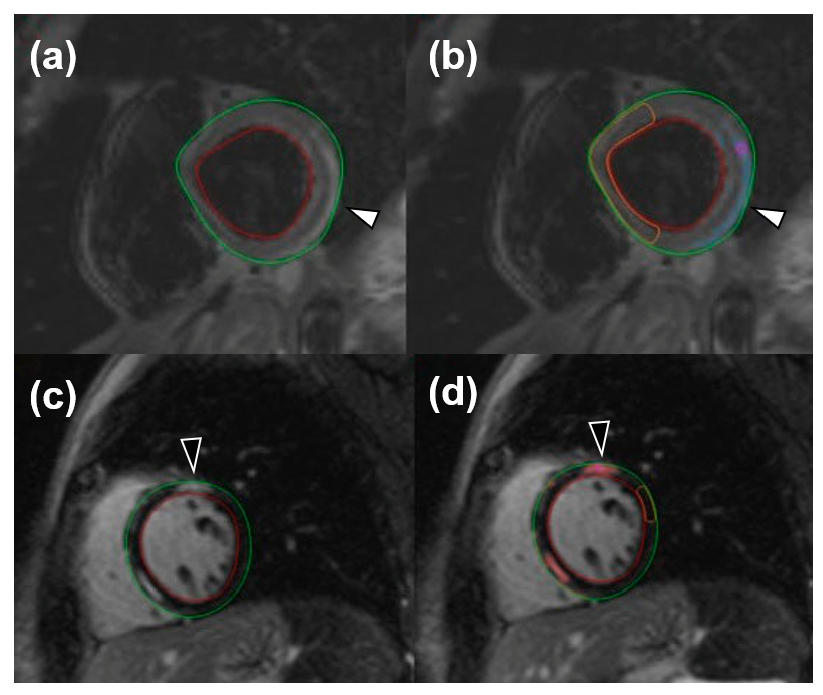

For image analysis, the QMass post-processing tool (Medis Suite MR Software, Medis Medical Imaging Systems, Leiden, The Netherlands) was used. Cine sequences were manually bordered to obtain left ventricle functional data such as end-diastolic volume index, end-systolic volume index, stroke volume, and ejection fraction. Short-axis turbo inversion recovery magnitude sequences were also manually bordered; a threshold of 2 standard deviations (SD) was used to identify edema. Short-axis LGE sequences were manually bordered, and a 6-SD threshold was used to identify enhanced areas. Image analysis for edema was performed twice by one reader and once by a different reader. An example of automatic LGE and edema quantification can be viewed in Figure 1.

Figure 1.

Short-tau inversion recovery images for the visualization of edema (white arrowheads) both without (a) and with (b) an automatic quantification mask of remote myocardium and late gadolinium enhancement (black arrowheads), without (c) and with (d) an automatic quantification mask of remote myocardium.